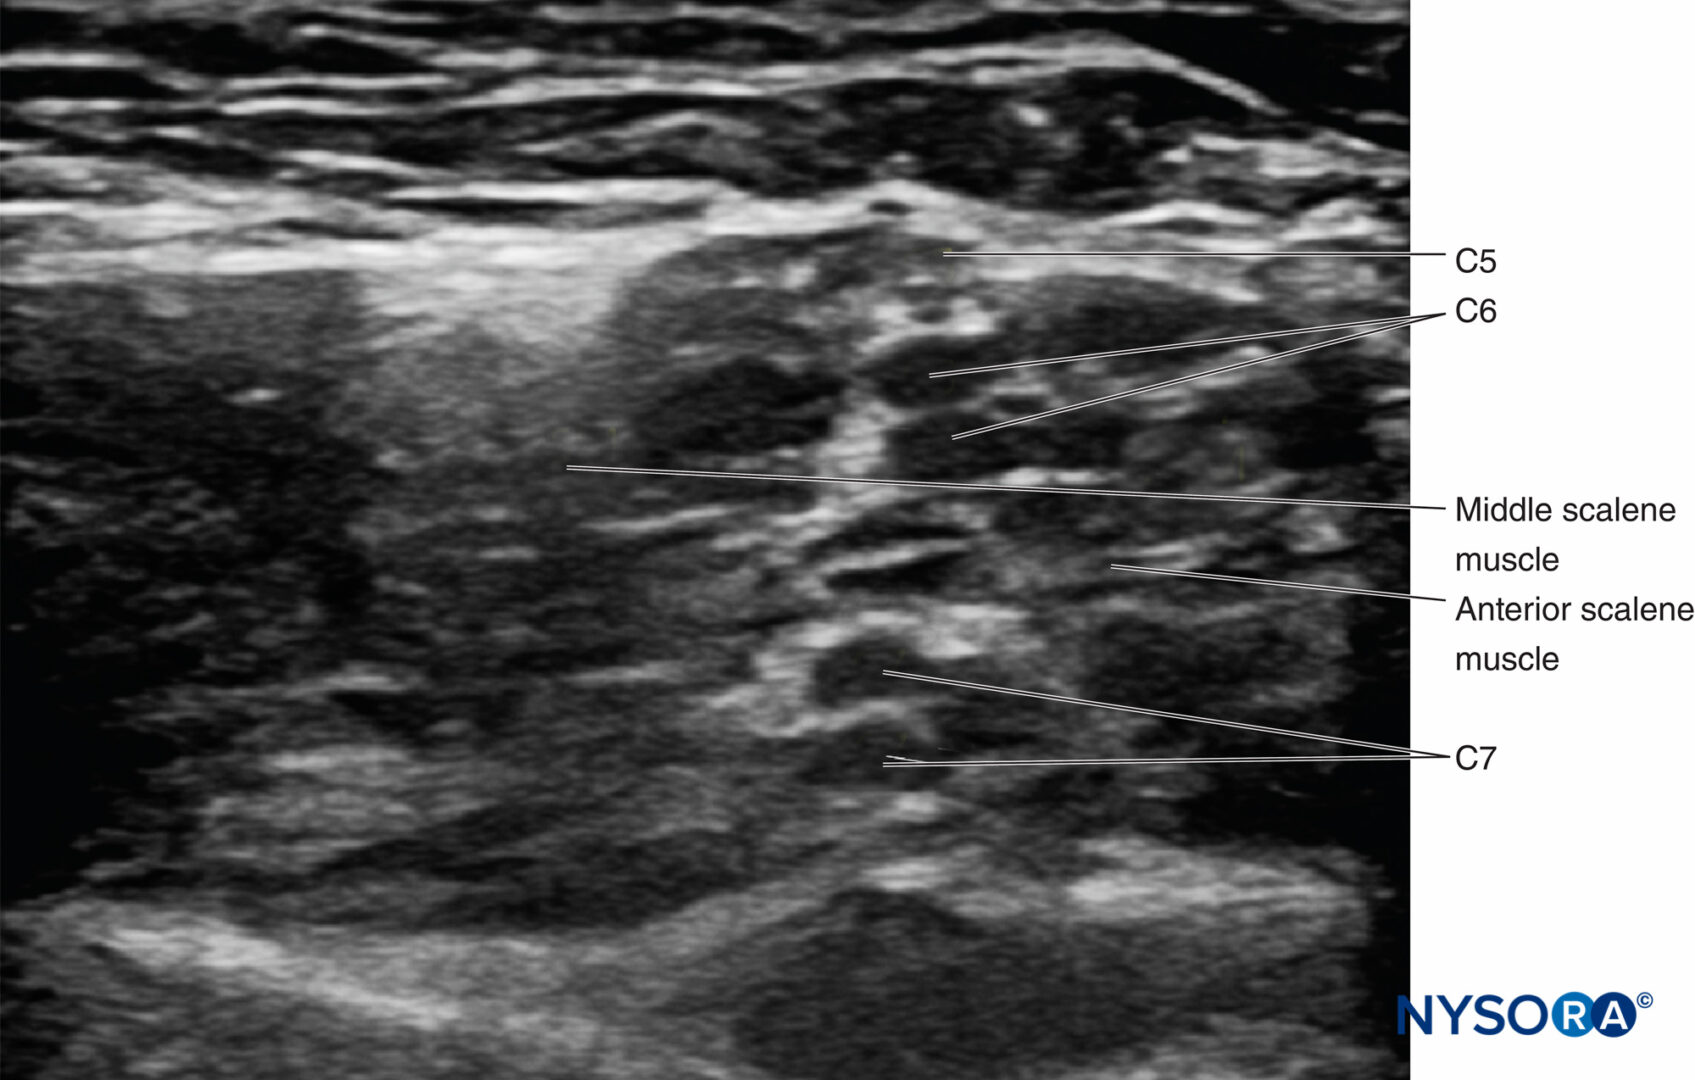

From www.nysora.com

UltrasoundGuided Interscalene Brachial Plexus Nerve Block NYSORA What Is An Interscalene Block The interscalene nerve block is a commonly performed regional anesthetic technique at the level of the upper trunks of the brachial plexus to provide anesthesia and analgesia for shoulder, upper. The interscalene block (isb) anesthetizes the brachial plexus at the level of the nerve roots, and is used for surgery of the upper. Interscalene block is well suited for surgical. What Is An Interscalene Block.